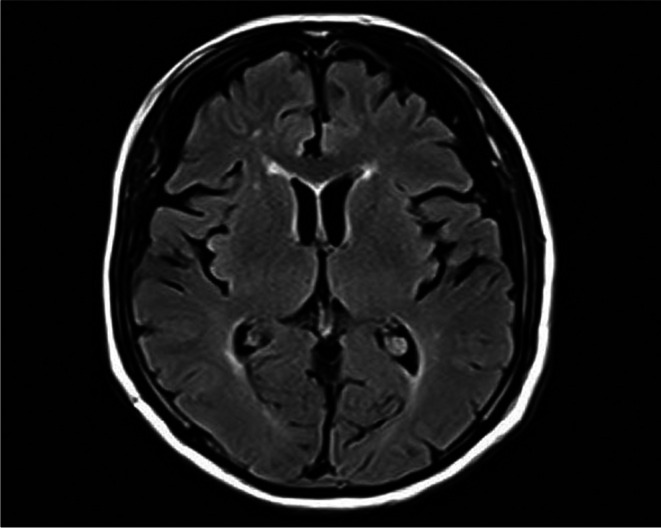

Case presentation: An 80-year-old male with no psychiatric history presented with flu-like symptoms, followed by the acute onset of neuropsychiatric symptoms, including pressured speech, agitation, memory impairment, and abnormal behavior. Autoimmune encephalitis was suspected due to mildly elevated cerebrospinal fluid (CSF) white cell count and a mass in the right upper lung detected by whole-body computed tomography (CT) on the first day of hospitalization. High-dose intravenous corticosteroids were administered on Day 1, resulting in prompt and sustained improvement in symptoms. CSF was later confirmed positive for anti-NMDAR antibodies, and a bronchoscopy biopsy of the pulmonary mass diagnosed SCLC. The patient recovered without neurological deficits and was discharged in stable condition on hospital Day 30.